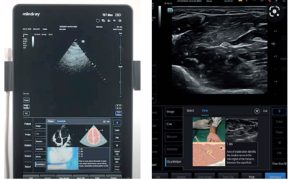

Z perspektywy organizacyjnej i systemowej ultrasonografia wspierana przez sztuczną inteligencję odpowiada również na jedno z największych wyzwań współczesnej medycyny – nierównomierny poziom kompetencji personelu oraz ograniczoną dostępność ekspertów. Badania pokazują, że rozwiązania AI-wspierające POCUS mogą istotnie zmniejszać różnice pomiędzy operatorami o różnym poziomie doświadczenia, poprawiając powtarzalność wyników i bezpieczeństwo procedur, szczególnie w środowiskach o ograniczonych zasobach kadrowych (4).

Z mojego doświadczenia dydaktycznego i obserwacji klinicznych wynika, że właśnie w ultrasonografii najbardziej widoczna jest zmiana paradygmatu: od technologii wymagającej wieloletniej nauki pod okiem eksperta do narzędzia, które, przy odpowiednim wsparciu algorytmów, może być efektywnie wykorzystywane przez szerokie grono lekarzy. Nie oznacza to oczywiście uproszczenia odpowiedzialności klinicznej, lecz raczej jej przesunięcie: z manualnej obsługi aparatu w stronę krytycznej oceny informacji dostarczanej przez system.

Proces ten rozpoczyna się już na etapie akwizycji obrazu. Algorytmy sztucznej inteligencji coraz częściej pełnią funkcję systemów prowadzenia użytkownika, pomagając w prawidłowym ustawieniu głowicy, doborze optymalnej projekcji oraz stabilizacji obrazu. Ma to szczególne znaczenie w warunkach intensywnej terapii i bloku operacyjnego czy szpitalnego oddziału ratunkowego, gdzie badania POCUS wykonywane są często w pośpiechu, w nieidealnych warunkach sonoanatomicznych i organizacyjnych. Dzięki temu możliwe staje się uzyskanie diagnostycznie użytecznych obrazów również przez lekarzy z mniejszym doświadczeniem ultrasonograficznym, bez obniżenia jakości badania (6).